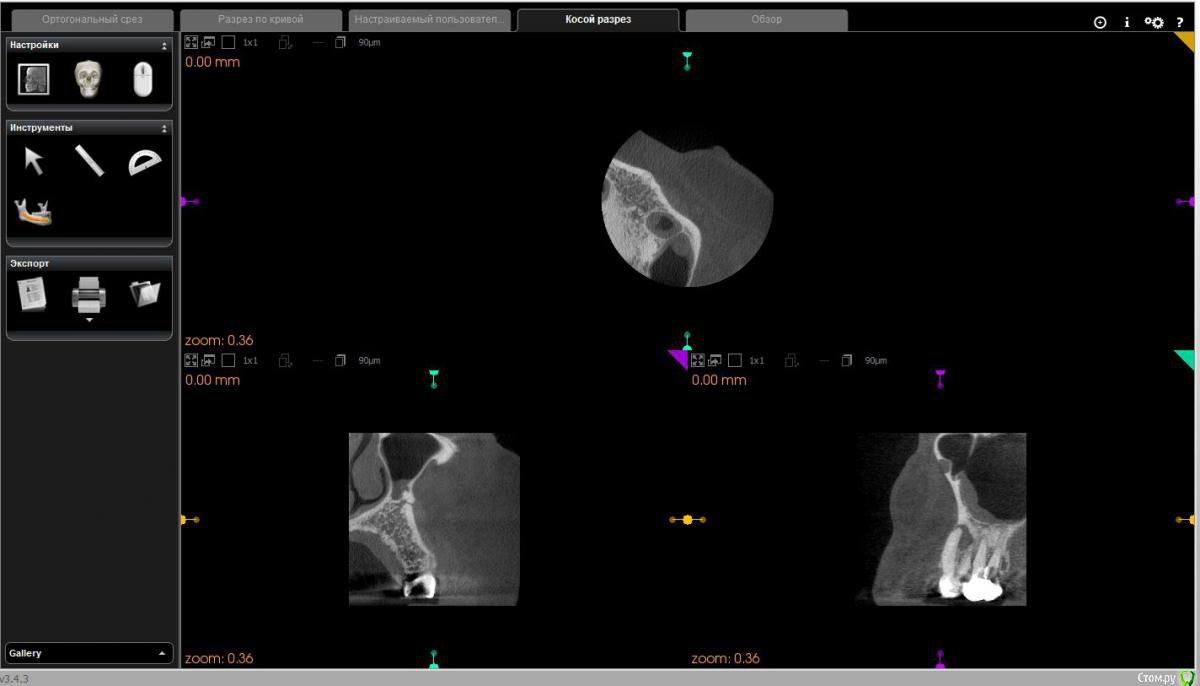

Диана135 Опубликовано 31 марта, 2017 Поделиться Опубликовано 31 марта, 2017 Здравствуйте! Год назад лечила зубы, осенью над одним из них появился флюс, который до сих пор не исчезает, это доставляет мне дискомфорт. Стоит ли продолжать лечение или проще удалить? Прилагаю описание КЛКТ: Зуб 2.6 коронковая часть восстановлена рентгеноконтрастным материалом. Трех корневой, четырёх канальный (в медиально-щечном 2 канала). В медиально-щечном корне каналы прослеживаются, в одном из каналов, в верхней трети определяются фрагменты рентгеноконтрастного материала. В небном корне в верхней трети рентгеноконтрастный материал. В средней трети корня определяется внутрикорневой очаг деструкции 2,2×3,7 мм с резорбцией дистального края и линией просветления от очага деструкции в медиальную сторону апикальной трети. В проекции медиально- и дистально-щечных корней определяется ограниченный очаг деструкции однородной структуры, с неровными контурами, с разрушением наружной кортикальной пластинки и распространением процесса в сторону корней 2.8 зуба. Кортикальная пластинка дна верхнечелюстного синуса в проекции деструкции истончена с набуханием слизистой до 4 мм.Зуб 2.7 Коронковая часть восстановлена рентгеноконтрастным материалом. Трех корневой, четырёх канальный (в медиально-щечном 2 канала). В каналах определяется рентгеноконтрастный пломбировочный материал: в медиально-щечном корне, один из каналов не обтурирован, другой не до верхушки, в дистально-щечном обтурация не до верхушки, в небном до апикального отверстия. В области верхушек медиально и дистально щечных корней определяется деструкция до средней трети длины корней, с расширением пространства периодонтальной связки.Отмечается общая горизонтальная убыль костной ткани до 3 мм. Ссылка на комментарий

Диана135 Опубликовано 1 апреля, 2017 Автор Поделиться Опубликовано 1 апреля, 2017 Скриншоты снимка. Ссылка на комментарий